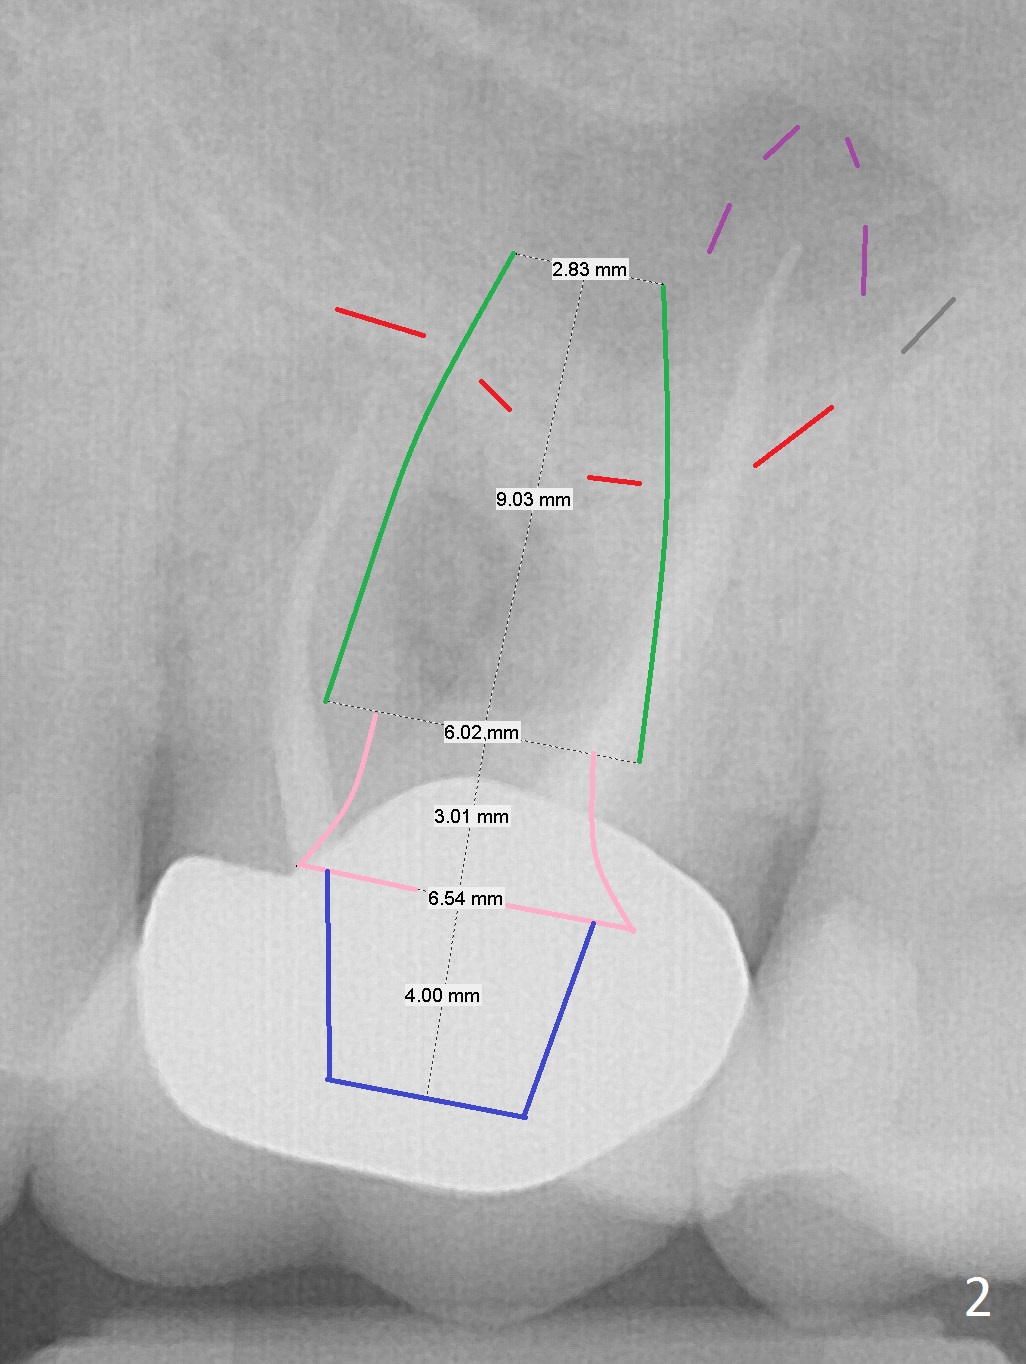

Place Implant Between Sinus Floor and Palatal Apex

A 70-year-old man will return for #14 extraction and implant placement after consultation with an endodontist (Fig.1). Note the large periapical radiolucencies associated with the mesiobuccal and palatal roots (*). After extraction and Metronidazole, start osteotomy in the septum, place PRF membranes/plug and allograft/Osteogen and then a dummy implant or tap. Place a large definitive implant (Fig.2 green) higher than the sinus floor (red), but lower than the palatal apex (purple).